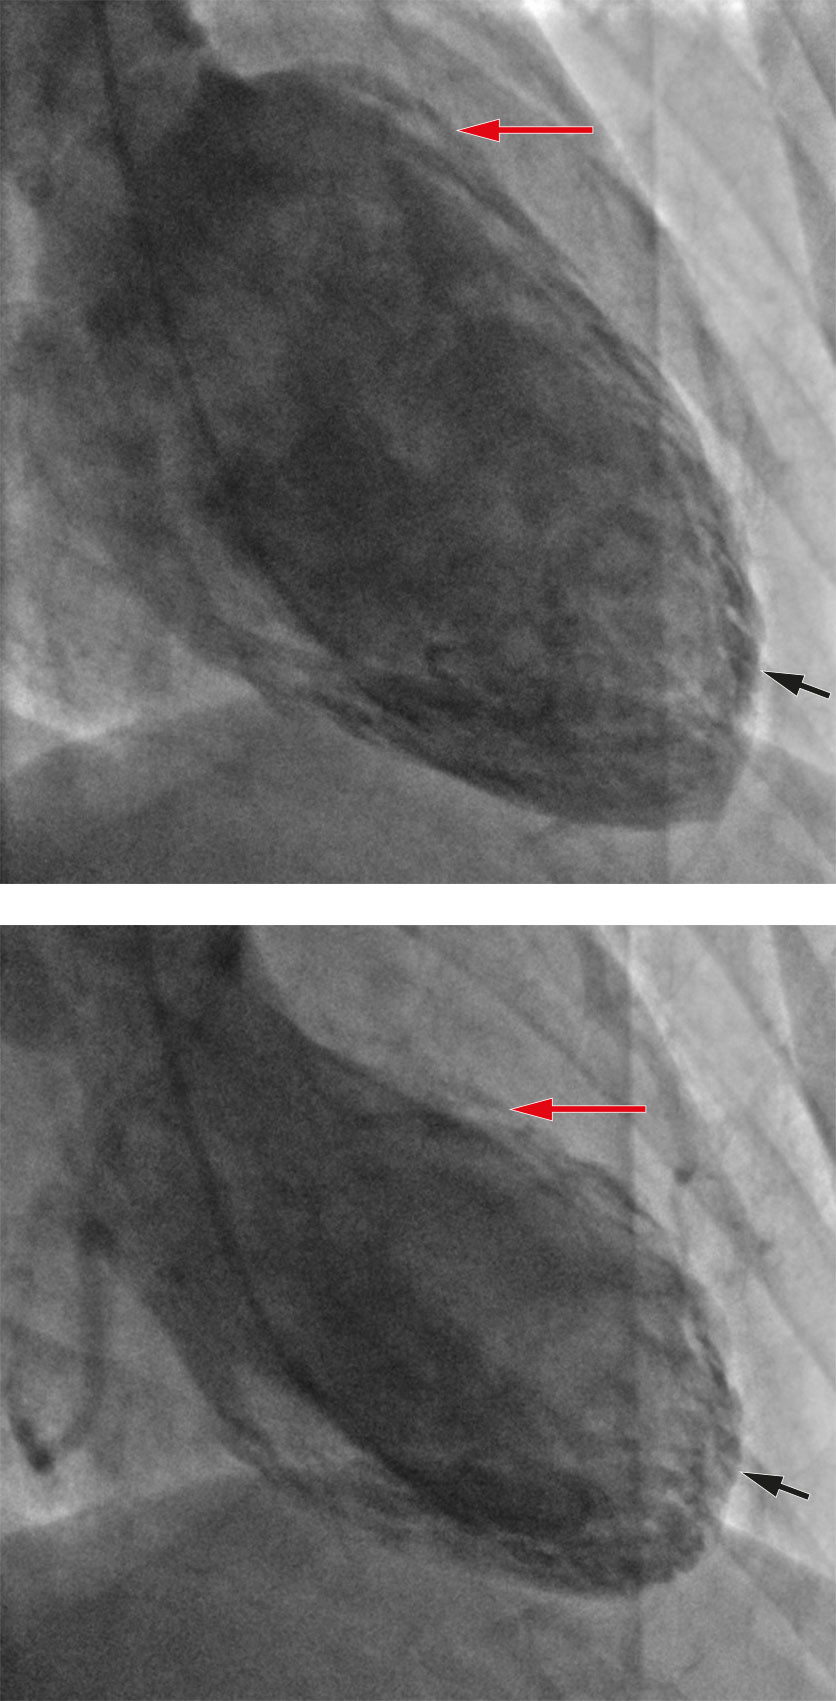

Koronarangiografi viste normale koronararterier, og ventrikulografi viste hypokinesi apikalt og hyperkontraktilitet basalt, typisk for takotsubosyndrom (Figur 2). Samme kveld ble det startet opp behandling med 1,25 mg ramipril.